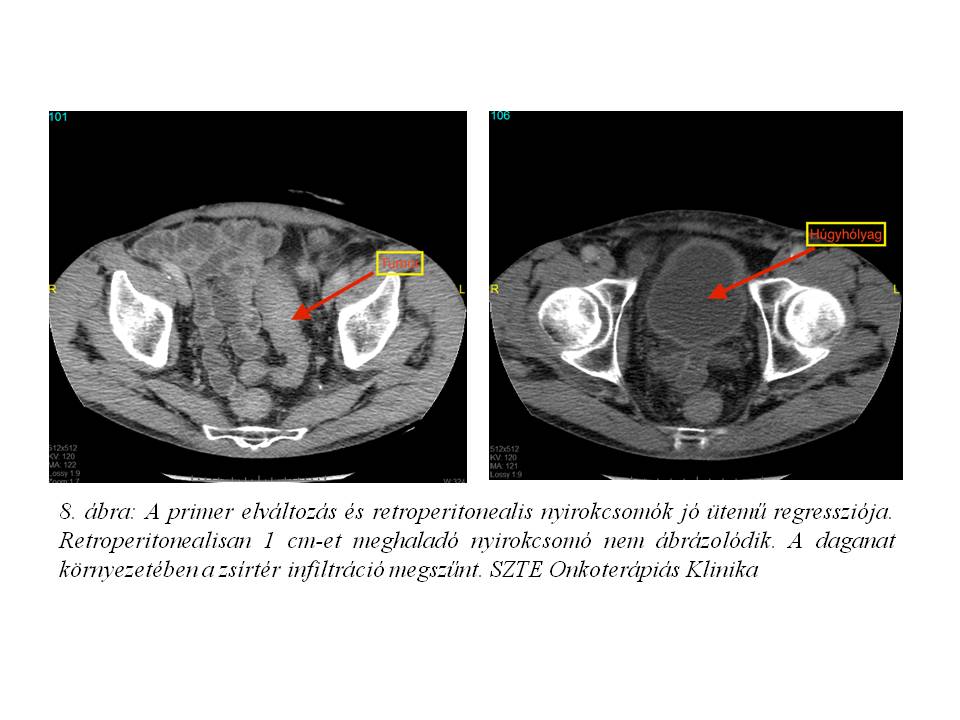

A neoadjuváns-kemoradioterápia sikeres komplettálását követően elvégzett re-staging has+medence CT jó ütemű regressziót igazolt mind az iniciális tumor, mind a nyirokcsomó státusz tekintetében (7. ábra, 8. ábra). Tekintettel a kedvező tumor válaszra 2014.11.05-én SZTE Sebészeti Klinikán sigma resectio és partialis húgyhólyag resectio történt. A szövettani feldolgozás közepesen differenciált cribriformis adenocarcinomát igazolt, ypT3yN0 (0/1 nyirokcsomó) stádiummal. A rezekciós szélek és hólyag nyálkahártyája intaktnak bizonyultak.